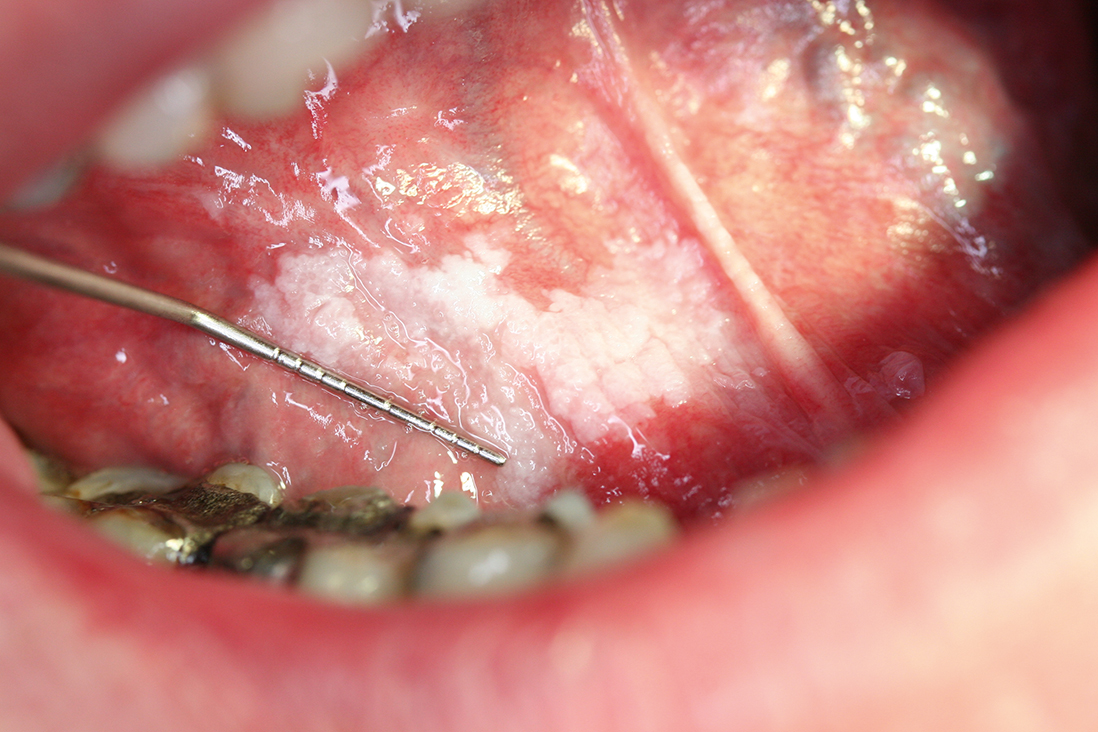

De patiënte bemerkte een witte verkleuring van de tong (leukoplakie) [figuur 1]. Deze premaligne afwijking ontaardt bij 24% van de gevallen in een maligniteit.6 Patiënten met een tongcarcinoom hebben vaak een zwelling of ulcus in de tong [figuur 2]. Aanvankelijk is deze asymptomatisch, maar bij doorgroei ontstaan pijnklachten en mobiliteitsverlies van de tong, waardoor spraak- en slikproblemen kunnen optreden. De pijn kan uitstralen naar de kaak, hals en oren. Bij onderzoek van de tong wijst een geïndureerde zwelling op een maligniteit. Verder let de huisarts op lymfadenopathie van de hals, vooral submandibulair en dorsaal van het kaakkopje. Een biopt van de laesie kan de diagnose bevestigen.

De aios in de casus stelde de werkdiagnose fibroom, een afwijking die veroorzaakt wordt door chronische irritatie van onder andere bijten of een slecht passende gebitsprothese. Een fibroom zit echter meestal op het wangslijmvlies of op de tongpunt, maar kan zich soms ook presenteren op de laterale tongrand. Een andere benigne tumor van de mondholte is het papilloom, een wratachtige afwijking veroorzaakt door het HPV-virus. Noch het fibroom, noch het papilloom geeft doorgaans pijnklachten en beide groeien exofytisch, in tegenstelling tot het tongcarcinoom [figuur 3].